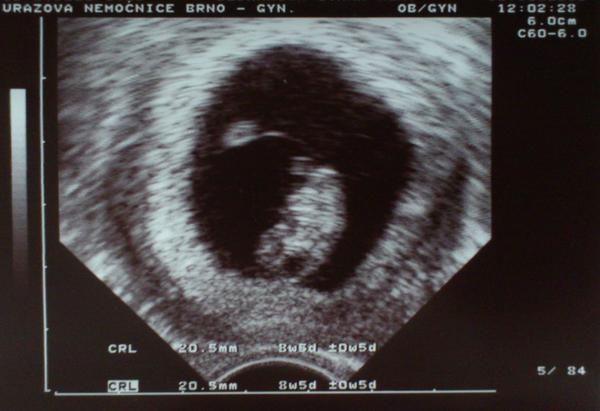

Ahoj kočky, tak včera dopadl utz na jedničku - končím 8. týden, máme 20mm a krásný srdíčko 😵

@pupidu to je skvely tak hod fotecku!

Jinak, tady je naše prdelka 😵